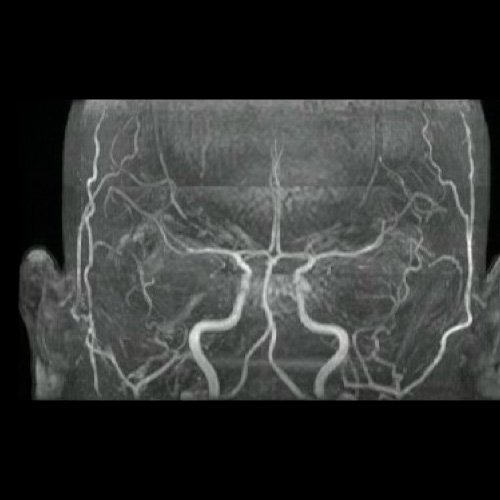

Curso internación en sala general y fue evaluada en conjunto con servicio de Neurología por síndrome atáxico en estudio. A su ingreso, se realizó Angio resonancia de cráneo que no evidenció alteraciones, se realizó una punción lumbar sin hallazgos de jerarquía, con posterior resultado negativo para virus de varicela zoster y herpes simple.

Anexo 3. Angio RMI de cráneo. Reconstrucción 3d.